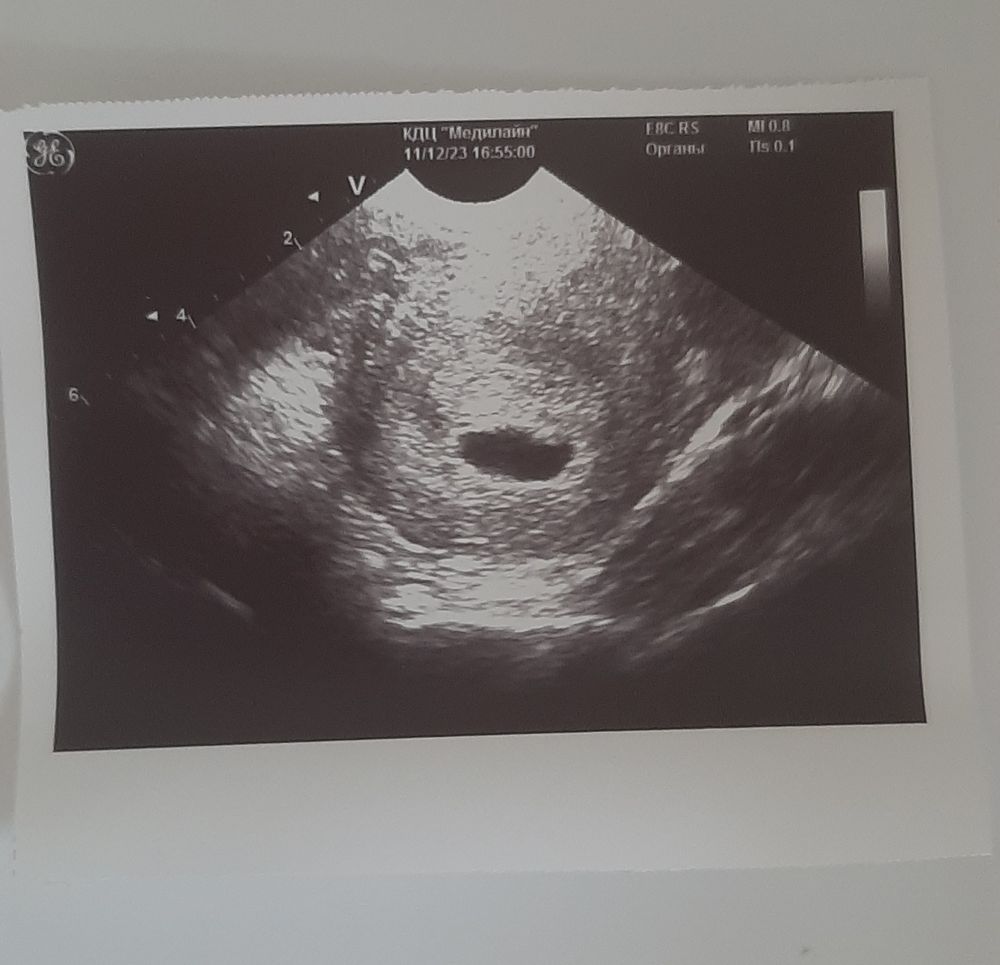

Беременность 6 недель, эмбрион не визуализируется

По УЗИ вообще ничего не понимаю.

Узист сказала прийти через неделю, проверить, сказала, что возможно овуляция поздняя, но я даже +- дни зачатия знаю, по календарю старались

УЗИ кажется не совсем корректным. Нет никаких данных о размерах плодного яйца, о желточном мешочке и жёлтом теле 🤷 Может вам в процессе УЗИ говорили что-нибудь о размерах и желточном мешочке?

Сказала, что беременность есть, но эмбриона пока не вижу, сб тоже нет.

Это не узи, а смех😂 Откуда в заключении беременность??? По эндометрию в 16 мм?😁где сведения о жт в яичнике? Где сведения о пя в матке?)))

Советую переделать УЗИ. Согласна с комментарием ниже, почему-то ни слова про желтое тело в яичнике, про плодное яйцо и его расположение, визуализируется оно вообще или нет. На основании чего в заключении беременность непонятно.

Странное узи, а где плодное яйцо и его размеры. Переделайте

УЗИ бред. Желтого тела нет. Оно должно быть. И если это пя, то почему ни слова о его размерах?